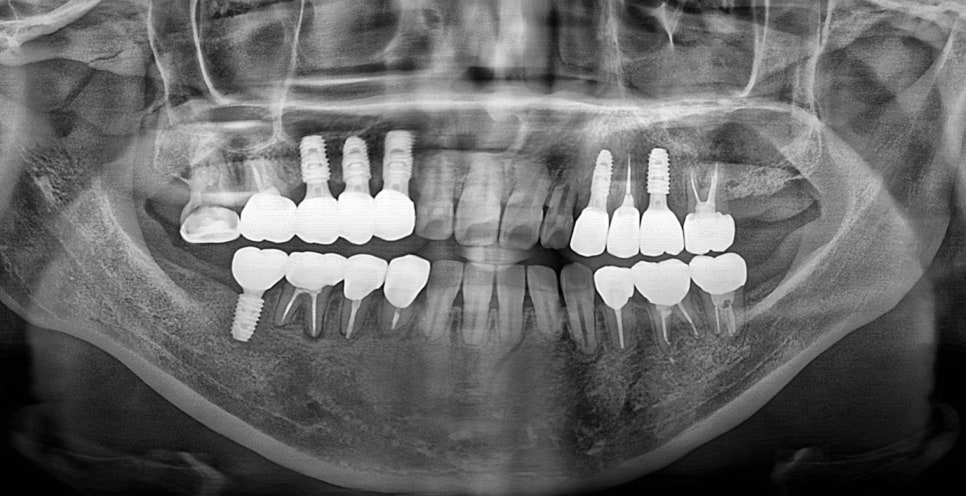

나이가 젊으신 분인만큼 최대한 살릴 수 있는 치아들은 살리고 임플란트 필요 치아들을 치료하는 방향으로 계획을 잡았습니다.

치조골이 소실 되어 있는 부분들은 뼈이식과 함께 진행 하였습니다.

위의 사진이 최종 치료 사진 입니다. 뼈이식, 신경치료 후 크라운, 임플란트 치료를 진행 하였고

최종 기간은 10개월 정도 소요 되었습니다.